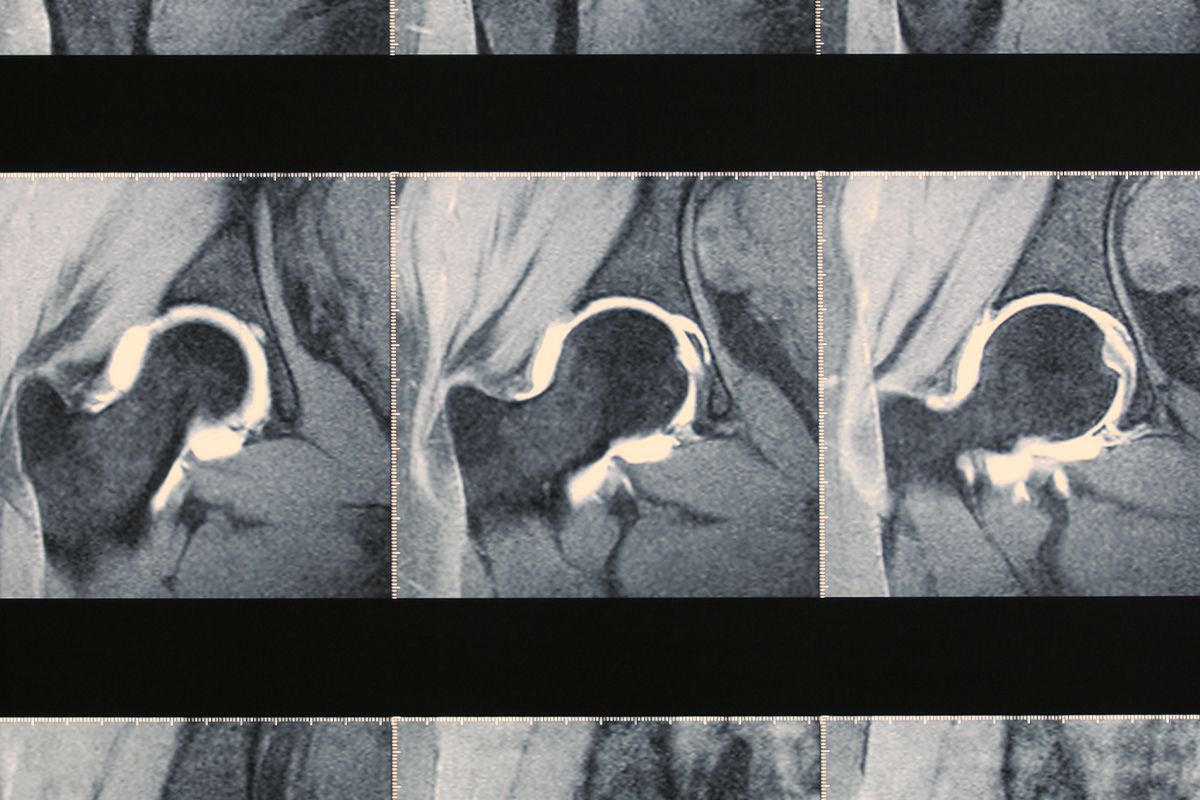

An arthrogram is a specialized imaging test used to examine joints more closely, particularly when other tests, such as a standard MRI or X-ray, do not provide a clear explanation for ongoing pain or mobility issues. It combines contrast dye with either MRI or CT imaging to give a clearer view of the soft tissues inside a joint, like ligaments, cartilage, tendons, and the joint capsule.

Unlike basic scans, arthrography allows radiologists to spot small tears, structural damage, or inflammation that may be missed otherwise.

While a standard MRI or CT can show the general structure of bones and soft tissue, an arthrogram adds contrast directly into the joint, helping to highlight movement and structure in a more detailed way. This is especially helpful when assessing joint injuries, surgical complications, or unexplained mechanical symptoms, such as locking or catching.

Arthrography is particularly useful when your physician suspects injury or damage to internal joint structures that can’t be seen well on routine imaging. This includes labral tears in the shoulder or hip, meniscus injuries in the knee, or ligament damage in smaller joints, such as the wrist.